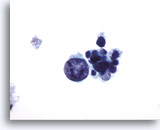

Negatief voor maligne cellen consistent met Hashimoto-thyroïditis

Wij zijn er achter gekomen dat ThinPrep niet optimaal is voor de diagnose van thyroïditis.[6] Hashimoto-thyroïditis wordt gekenmerkt door lagen of groepen folliculaire cellen met variërende mate van Hürthle-celveranderingen op een achtergrond van variërende aantallen lymfocyten en plasmacellen met incidenteel lymfoïde en folliculaire kernaggregaten. Omdat lymfocytisch/Hashimoto-thyroïditis een veelvoorkomende bevinding is bij de schildklier, is de monsterverzameling essentieel bij het uitsluiten van andere eveneens voorkomende en meer belangrijke laesies.